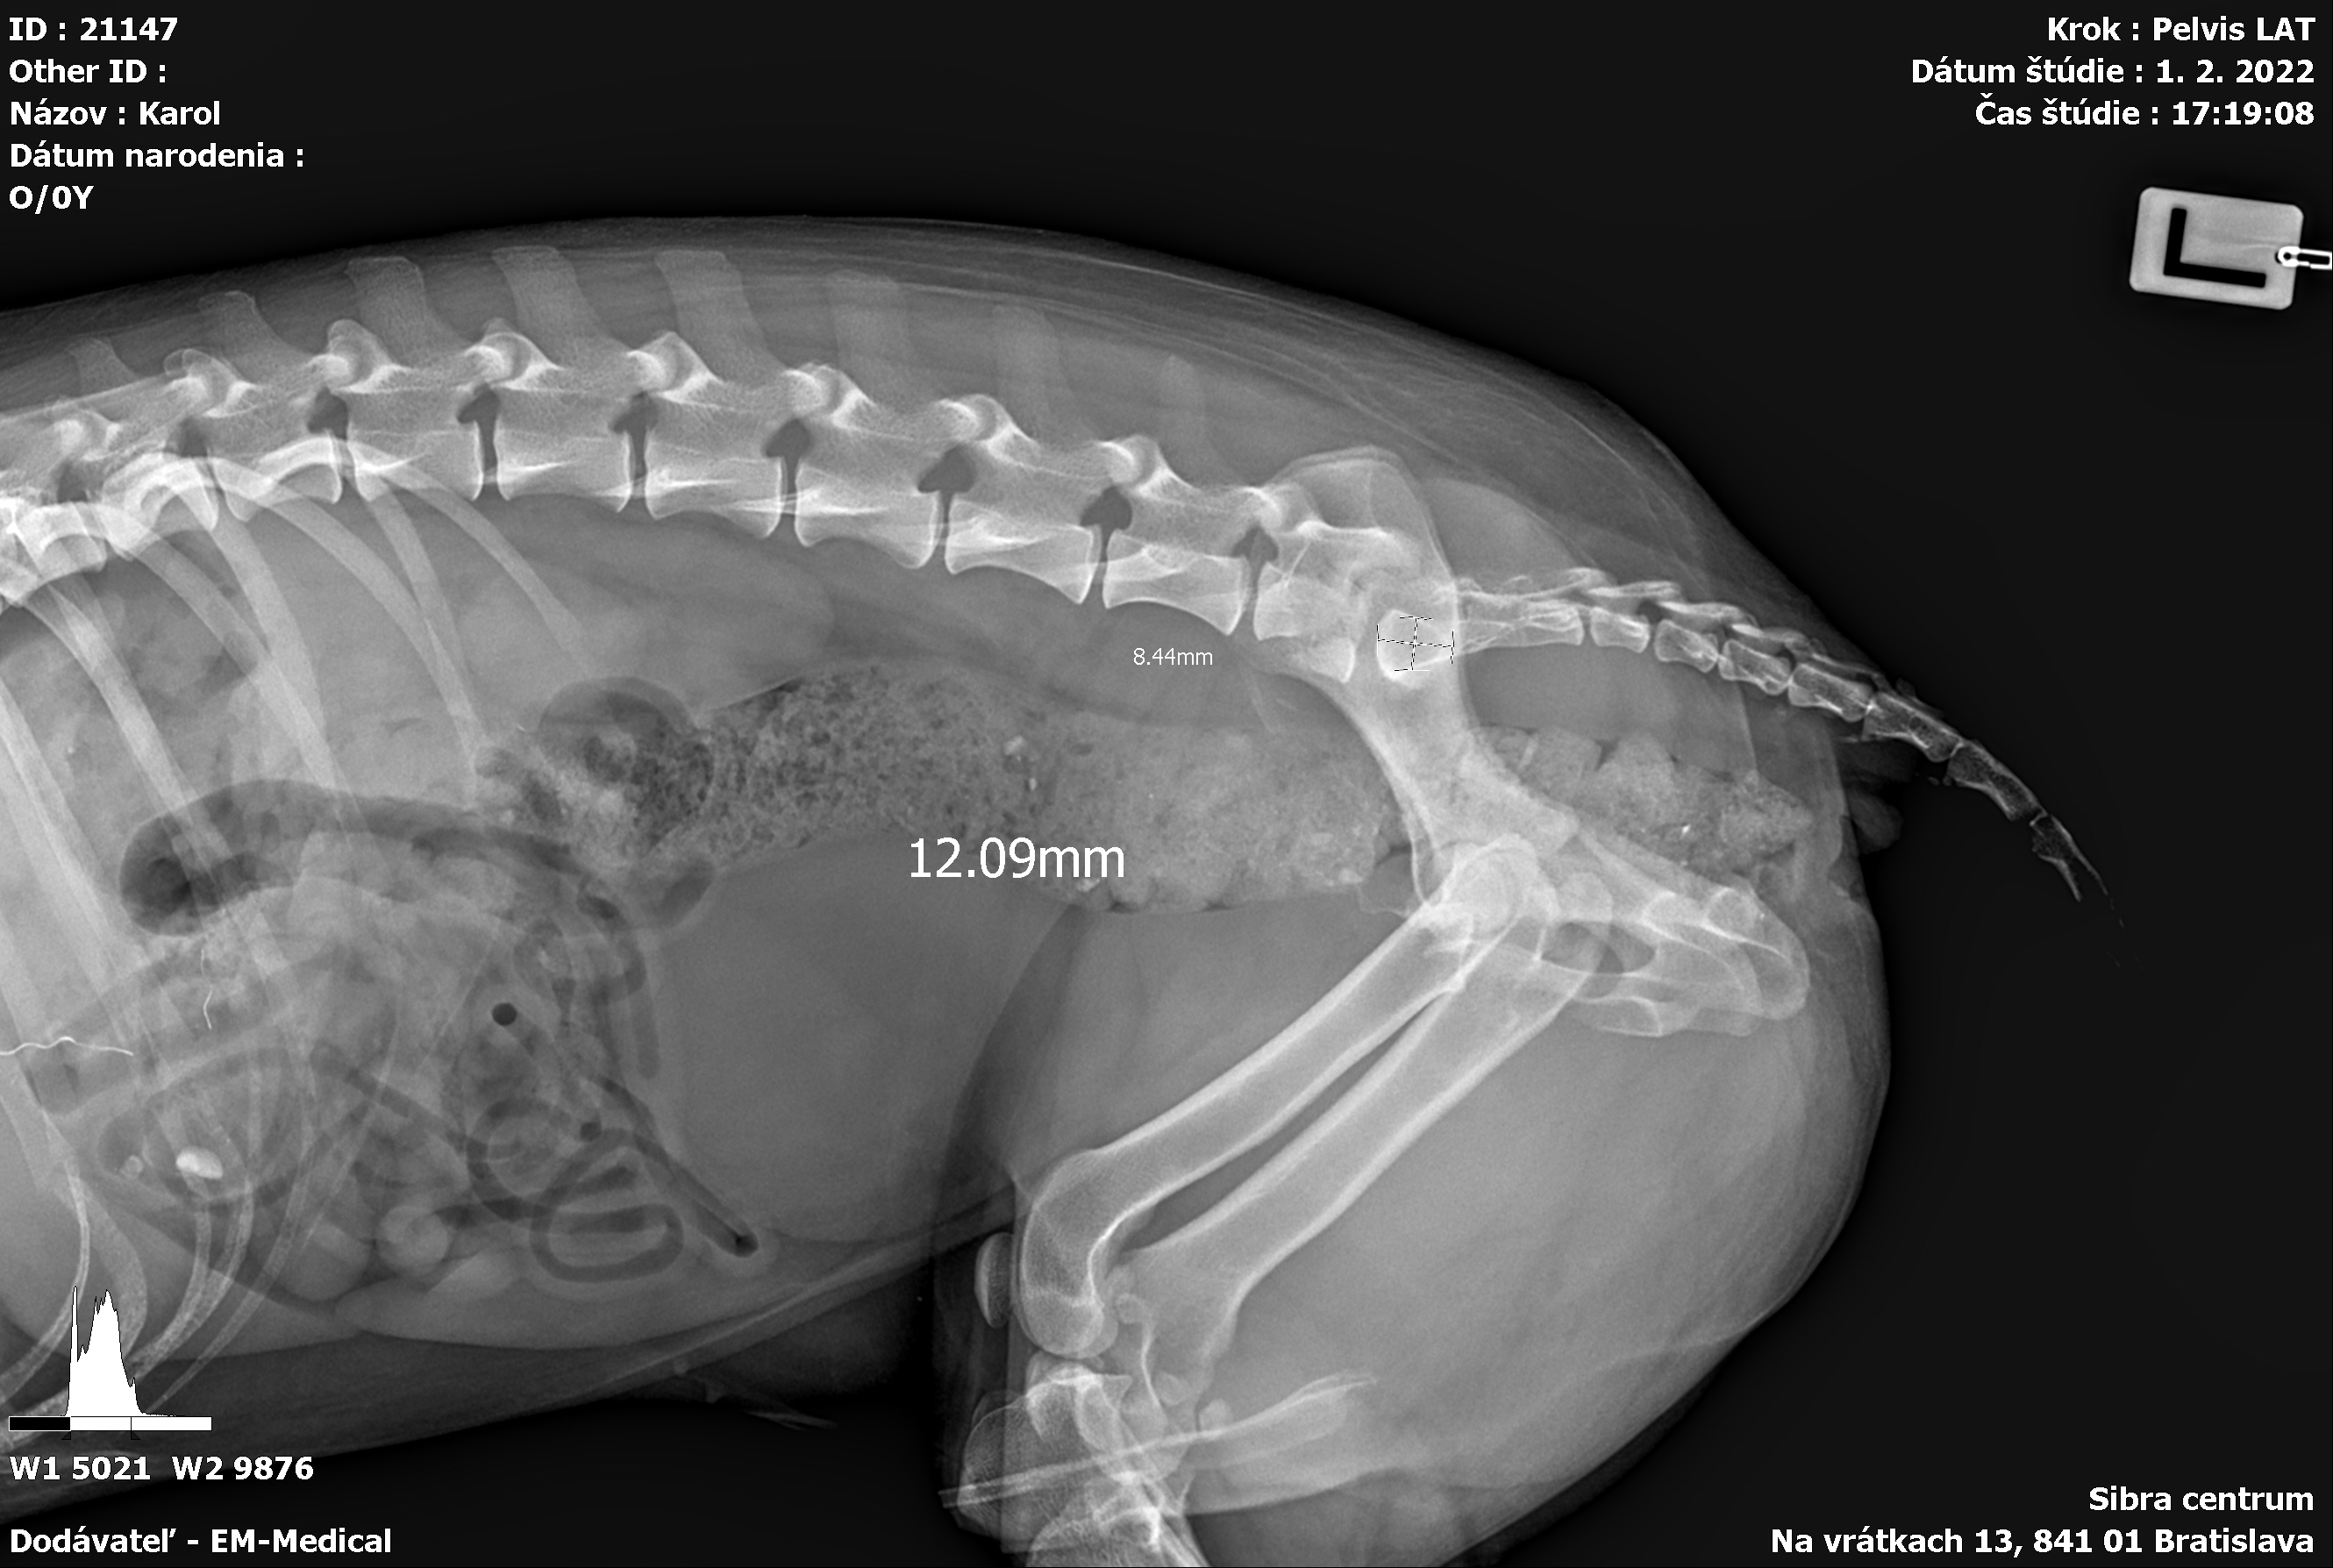

Karola nám doviezla pani, ktorá ho našla, asi jediná dobrá duša, ktorá pri ňom neprešla so zatvorenými očami. Ihneď sme s krpcom utekali na veterinu aby sa zistila závažnosť jeho zranení. Hneď pri prvých RTG snímkoch sa ukázala obojstranná fraktúra panvy, taktiež fraktúra krídla panvy a keby mu to chudákovi nestačilo, do tretice sa objavila zlomenina stavca. Karolko mal neznesiteľné bolesti, ale krásne prečkal vyšetrenie lebo vedel, že je v dobrých rukách a dostáva sa mu pomoci. Po nálezoch sme okamžite kontaktovali neurológiu a ortopédiu na veterinárnej klinike Sibra - centrum veterinárnej medicíny, kde sme dostali hneď termín na príjem.

Karol nemá žiadne neurologické deficity, po ortopedickej operácii bude vedieť behať a bez problémov bude vedieť samostatne cikať a kakať. Po tejto úžasnej správe sme samozrejme dali zelenú náročnej ortopedickej operácii pod vedením MVDr. Vatolíka. Operácia sa podarila na výbornú, Karči je "zoskrutkovaný" a vôbec nič mu nebráni v tom, aby opäť mohol behať a aktívne žiť. Momentálne sa zotavuje po operácii, musí mať prísny kľudový režim. Po vybratí stehov ho čaká hydro- a fyzioterapia, ktorá mu pomôže postaviť sa na nohy. Je to bojovník, veľmi sa chce uzdraviť a v jeho očkách je dokonale vidieť, že už kuje plány čo všetko zameškané bude musieť dobehnúť.